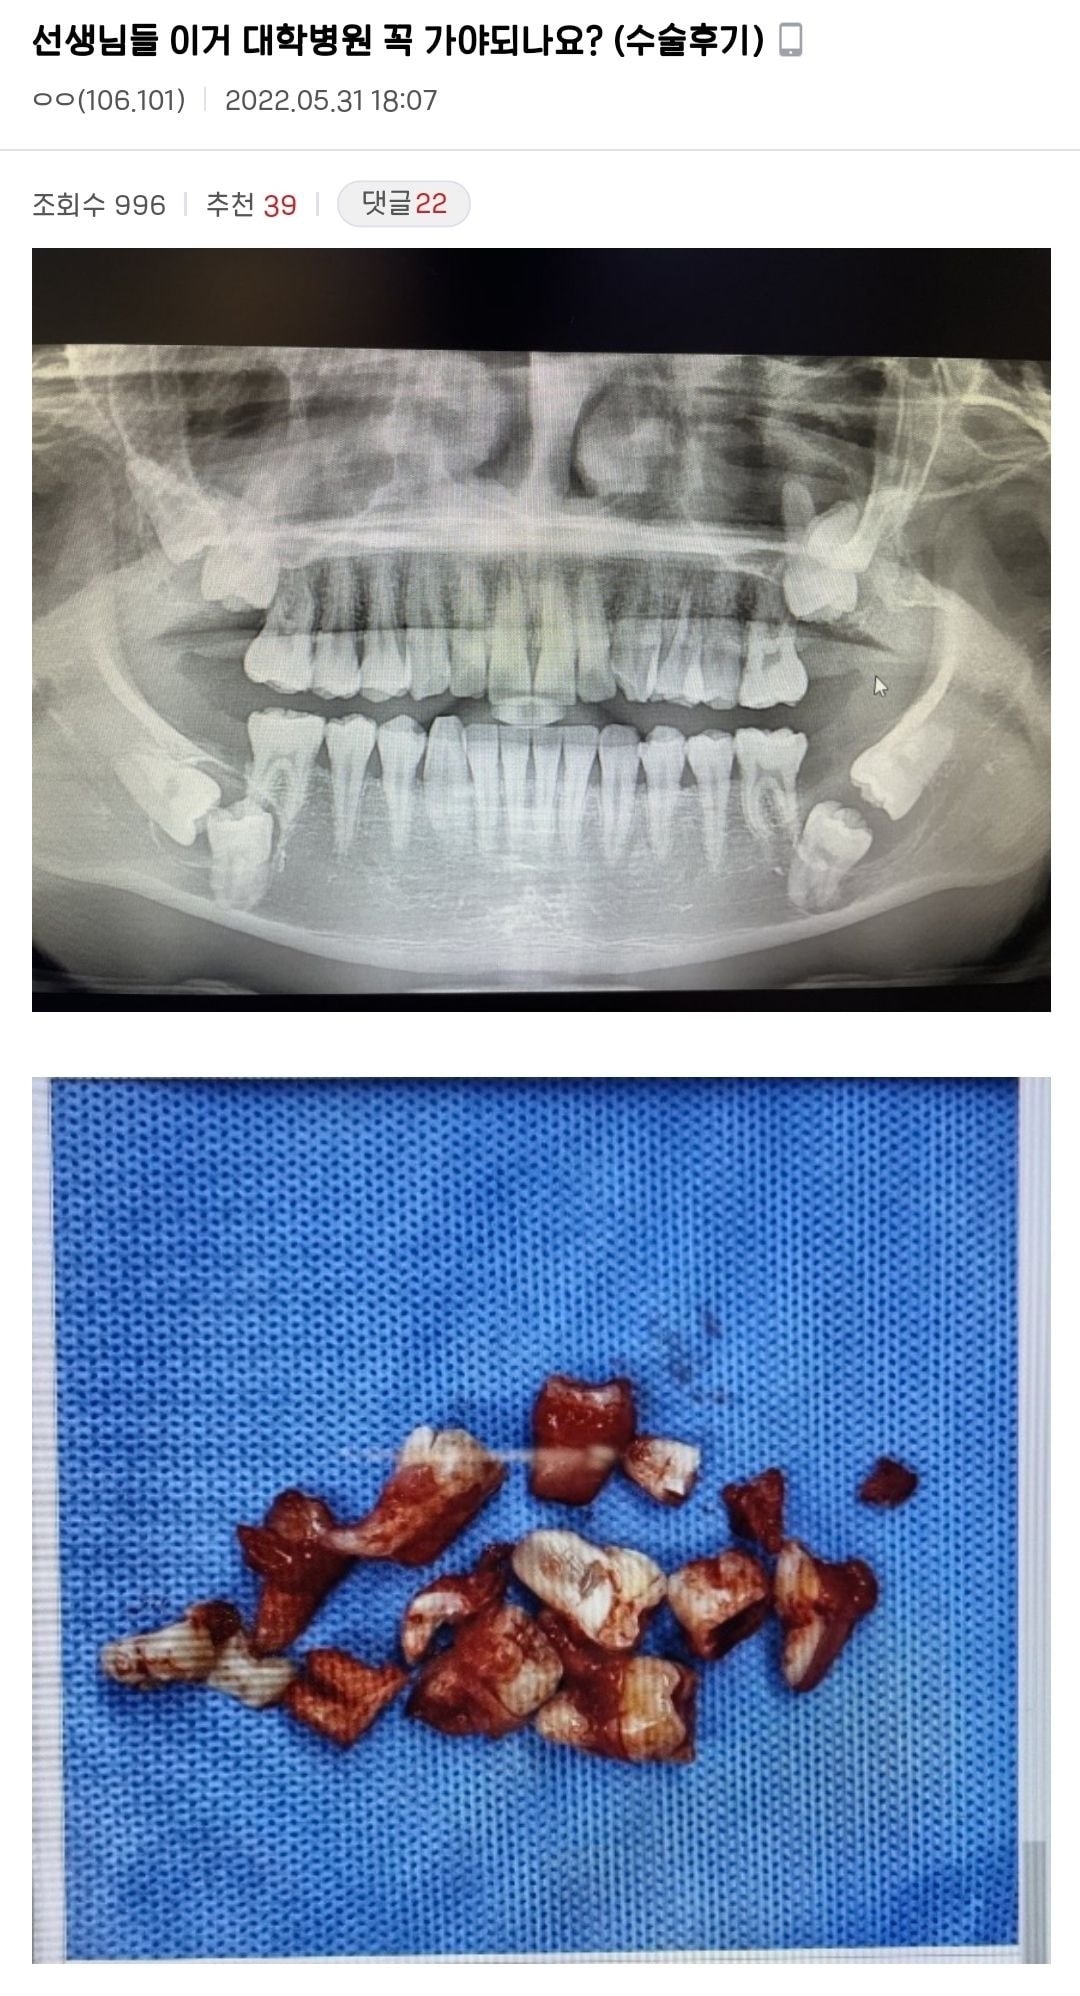

😬¼±»ý´Ôµé À̰Š´ëÇк´¿ø ²À °¡¾ßµÇ³ª¿ä? ÈıâÆ÷ÇÔ

»ç¶û´Ï°¡ °¢°¢ 2°³¾¿, ÃÑ 8°³¾ß!! ¹°·Ð Àú Áß 4°³´Â ¿ø·¡ ¾î±Ý´Ï¿´°ÚÁö¸¸¡¦ ¤Ð¤Ð

°³¼ö·Î º¸¸é... 7¹ø ¾î±Ý´Ï°¡ ´Ù ¸Åº¹ÀÎ »óÅÂ°í »ç¶û´Ïµµ 4°³.. ±×°Íµµ ¾ÆÁÖ ¾û¸ÁÁøÃ¢À¸·Î.... Àú°É ÇÑ ¹ø¿¡ ´Ù »¬ ¼öµµ ÀÖ±¸³ª... ¿À¤Ã... Ä¡¾Æ »Ñ¸® ¹æÇâ ºÁ....

½ºÄÉÀϸµ°¡¼ ¿¢½º·¹ÀÌ »çÁø±îÁö ÂïÀº°Å¸é. ½ºÄÉÀϸµ °øÂ¥·Î ÇØÁØ´Ù°í µ¥·Á¿Í¼ »çÁøÁ» Âï°í ÃæÄ¡°°Àº°Å Ä¡°úÄ¡·á ¹Þ°Ô ÇØ¼ º»Àüã´Â ¸¶ÄÉÆÃÇϴµ¥ °£°Å °°Àºµ¥... °Å±â¼ »çÁøÂï°í ¾ó¸¶³ª ³î¶úÀ»±î.. ¿ì¸®°¡ »ó´ëÇÒ »óŰ¡ ¾Æ´Ï³×.... Å«º´¿ø °¡¼¼¿ä....